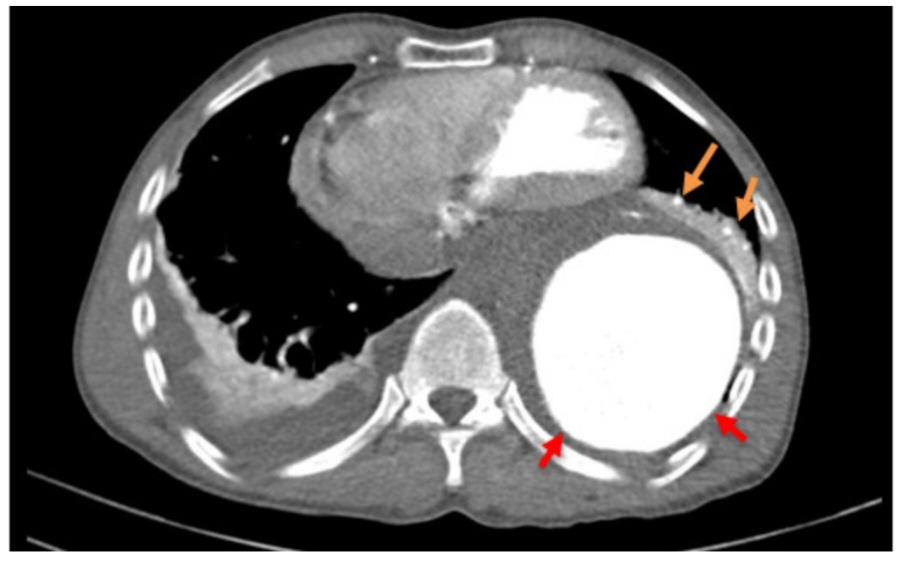

Bệnh nhân được đưa vào khoa cấp cứu Bệnh viện S.I.S, kết quả chụp CTA ông T bị phình động mạch chủ ngực đã vỡ gây tràn máu ra ngoài thành mạch xung quanh động mạch chủ ngực đoạn xuống và màng phổi hai bên, có nguy cơ tử vong cao. Chụp CT lồng ngực cho thấy máu tụ quanh phình động mạch chủ.

Screenshot_20230618_072436_WordChụp CT lồng ngực có tiêm thuốc cản quang: máu tụ quanh phình động mạch chủ. Ảnh BVCC